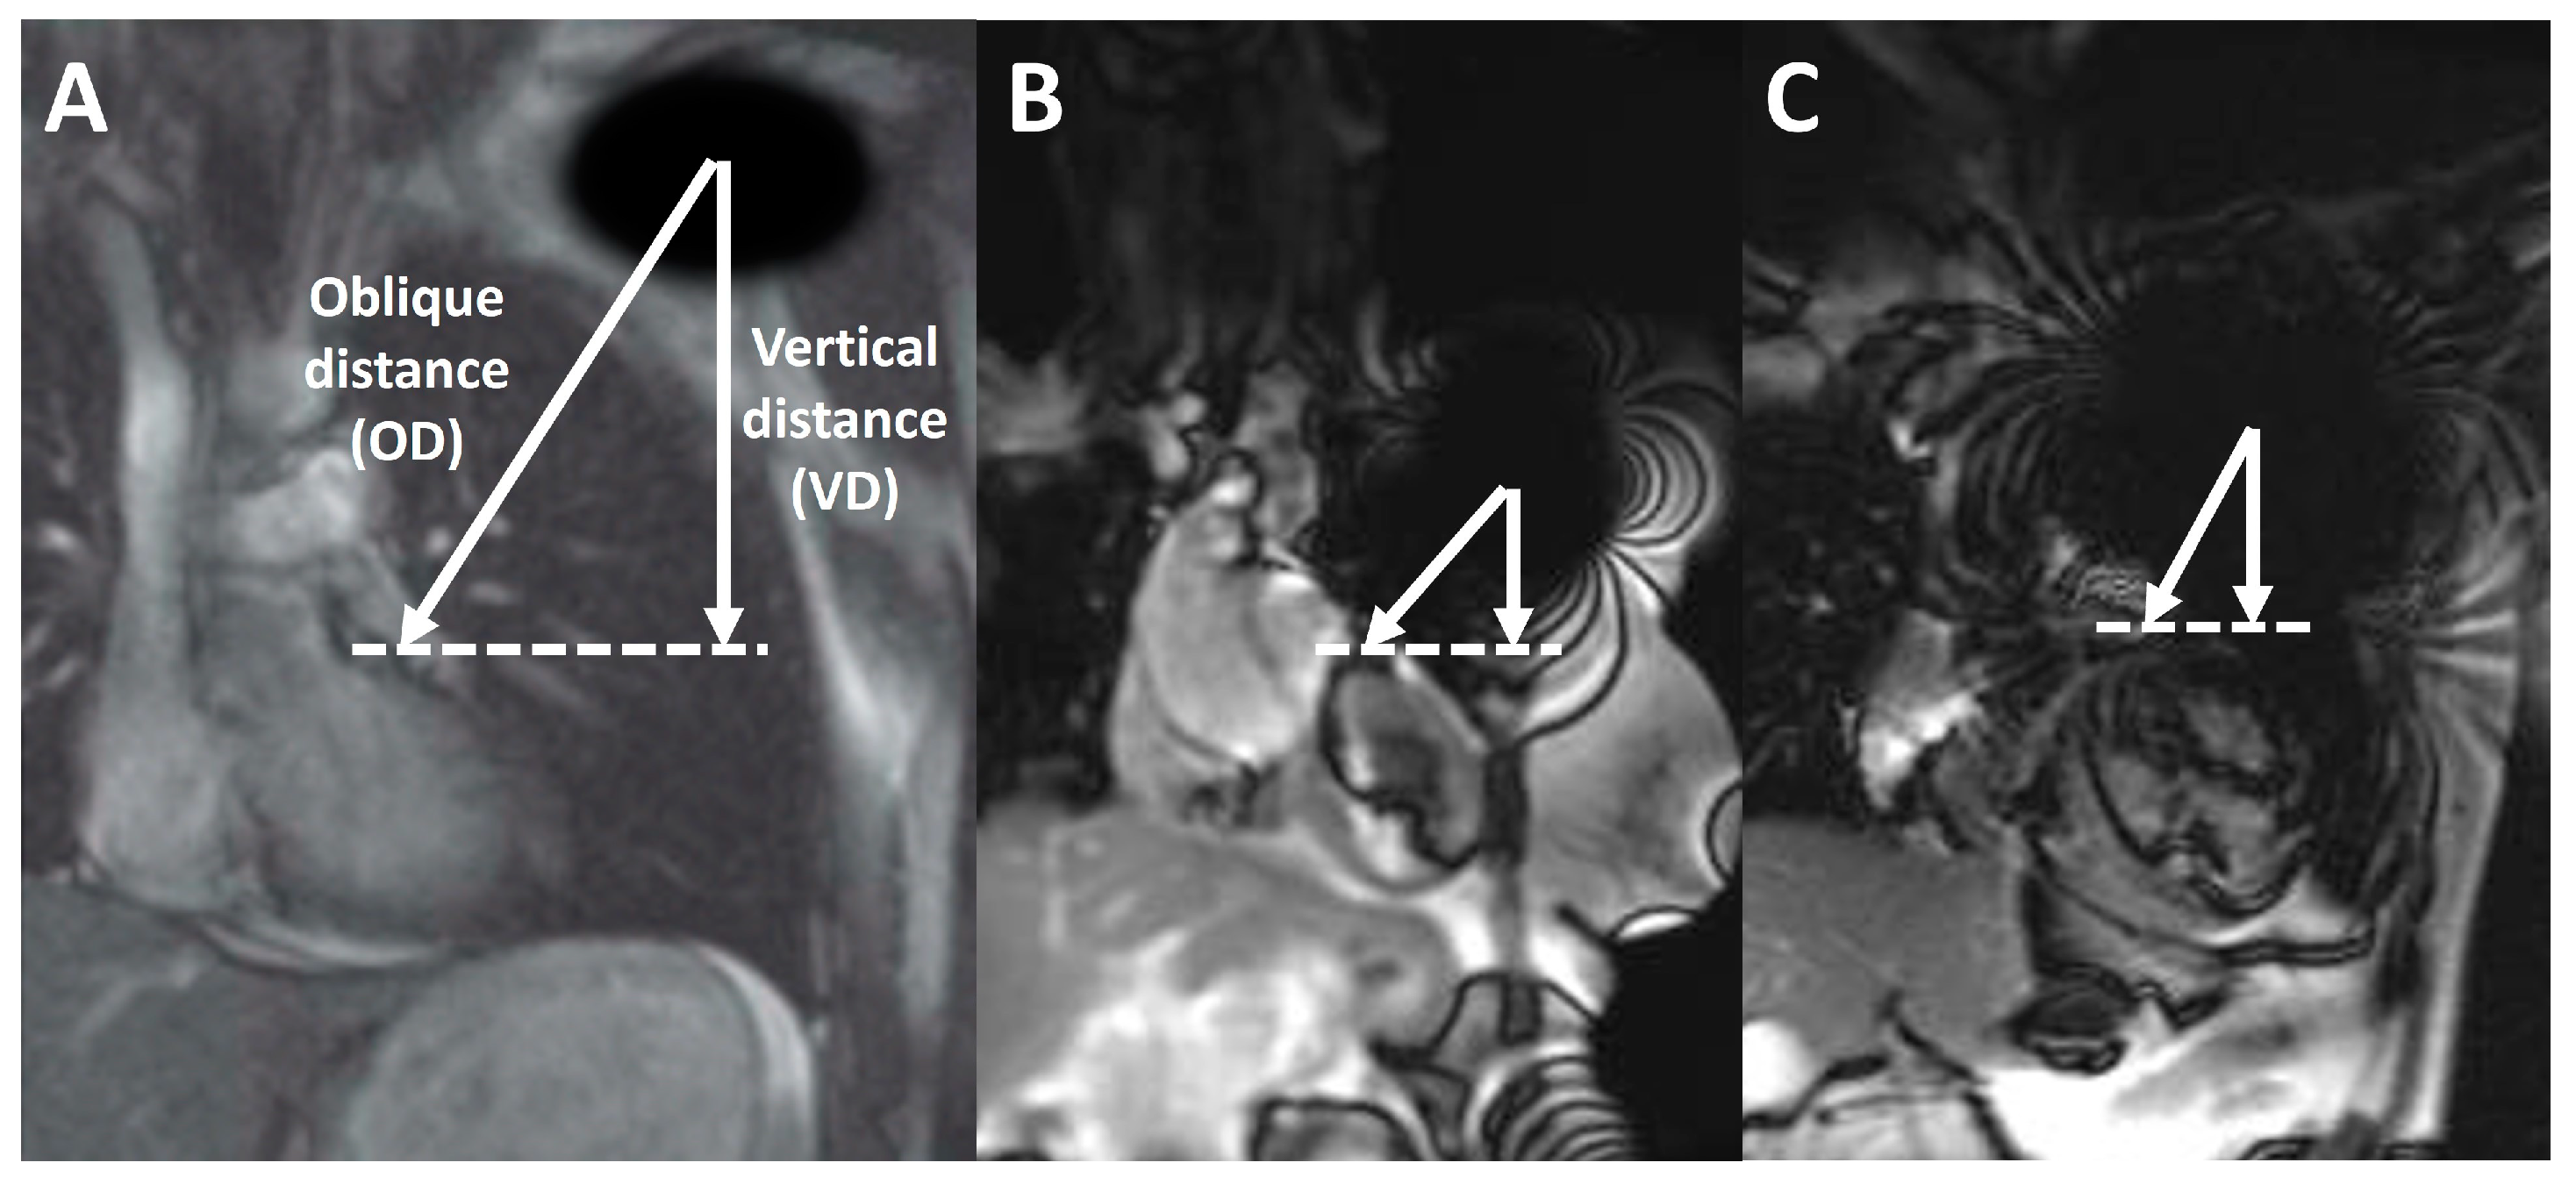

洋書 Cardiovascular Magnetic Resonance, 2e Open access information - Journal of Cardiovascular Magneticの詳細情報

Open access information - Journal of Cardiovascular Magnetic。洋書 Cardiovascular Magnetic Resonance, 2e Cardiovascular。洋書 Cardiovascular Magnetic Resonance, 2e Cardiovascular。

Society for Cardiovascular Magnetic Resonance/European

Society for Cardiovascular Magnetic Resonance/European